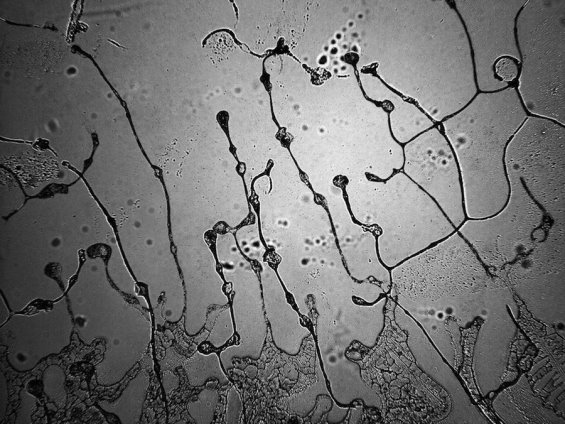

ที่ขึ้นๆลงๆ เป็นปล้องๆ มักเห็นชัดเวลากลอกตาในแสงสว่าง คืออะไรครับ